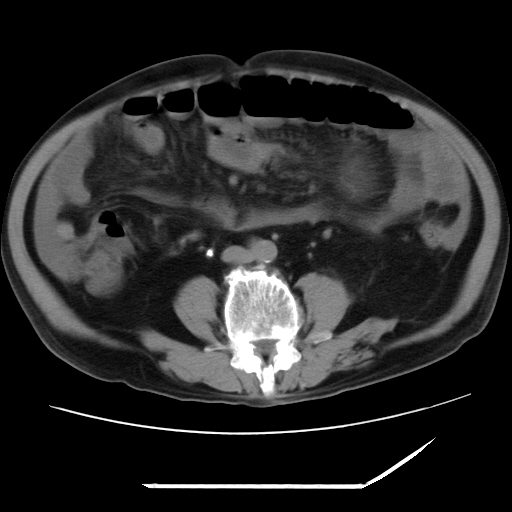

以下是引用zxl51642在2009-8-12 18:55:00的发言:[br]1、肠系膜脂肪浑浊,密度增高,腹水,支持腹膜炎诊断;2、右肾盂及输尿管中段结石,左输尿管起始段结石;3、胆囊切除术后改变?4、双侧胸膜腔少量积液;5、胰腺体积不大,勾勒清楚,肾前筋膜无增厚,不支持胰腺炎,请结合血尿淀粉酶及临床。

以下是引用黑白光影在2009-8-12 22:06:00的发言:[br][quote]以下是引用zxl51642在2009-8-12 18:55:00的发言:[br]1、肠系膜脂肪浑浊,密度增高,腹水,支持腹膜炎诊断;2、右肾盂及输尿管中段结石,左输尿管起始段结石;3、胆囊切除术后改变?4、双侧胸膜腔少量积液;5、胰腺体积不大,勾勒清楚,肾前筋膜无增厚,不支持胰腺炎,请结合血尿淀粉酶及临床。